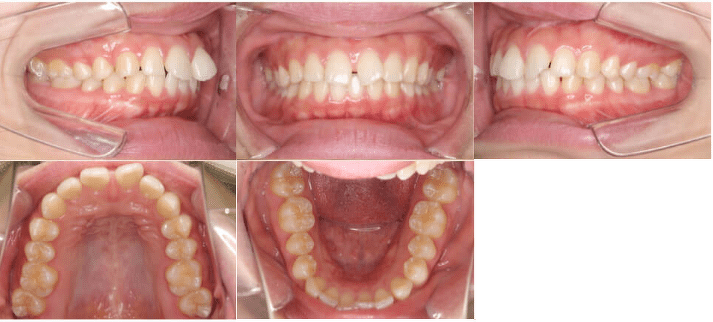

| 年齢 | 治療期間 | 費用 | 主訴 | 治療方法 |

| 7歳4ヶ月 | 9ヶ月 | 40万円 | 前歯のすきっ歯を治したい | マウスピース型矯正装置(インビザライン・ファースト 薬機法対象外) |

患者さんは前歯の隙間が気になると来院されました。前歯の真ん中に隙間がある「正中離開」と前歯の噛み合わせが深い「過蓋咬合(かがいこうごう)」の症状がみられ、また前歯の間に隙間が空いていることで、前歯の脇のまだ永久歯が生えていない場所が狭くなっていました。

この症例では、マウスピース型矯正装置(インビザライン・薬機法対象外)で非抜歯の9ヵ月の矯正治療を行いました。前歯の隙間を閉じて永久歯の生えるスペースを確保し、前歯の重なりを小さくすることで噛み合わせが改善されました。矯正治療でスペースを開けたため、治療前にはまだ生えていなかった永久歯が正常な向きに伸びてきています。